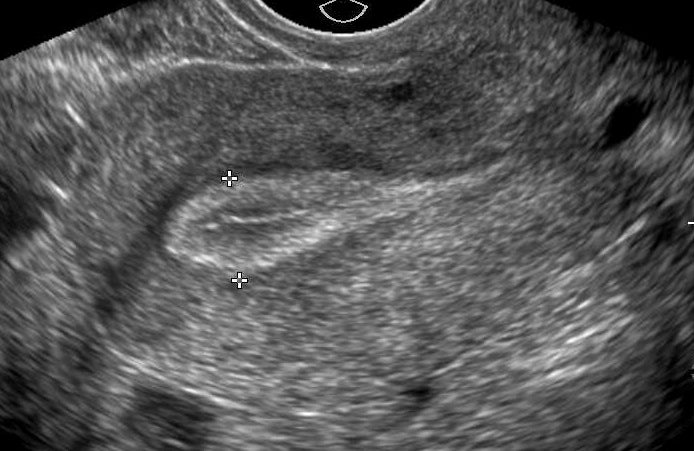

The endometrial lining scan is performed to assess the appearance and measure the thickness of the endometrial lining prior to embryo transfer.

- Scan to measure the thickness and assess the appearance of the endometrium